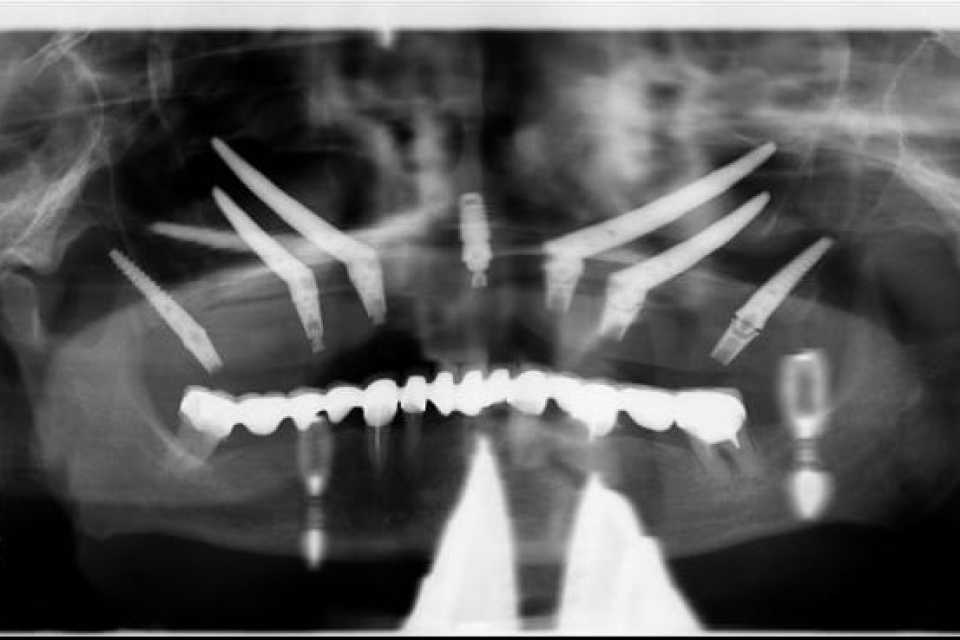

Pacienta, în vârstă de 75 de ani, veche purtătoare de proteza totală maxilară, trecută prin 2 adiții osoase și implanturi nereușite, se prezintă în cadrul clinicii cu dorința găsirii unei soluții de reabilitare protetice fixe a maxilarului.

Împreună cu pacienta am optat pentru implanturi orale speciale,o ultima soluție pentru pacienții cu atrofie osoasă severă.

Sub anestezie generală s-au inserat 4 implanturi zigomatice și 2 implanturi pterigoide și 1 implant dentar normal cu ajutorul cărora am realizat o lucrare dentară protetică fixă din ceramica pe zirconiu insurubabila de 14 elemente.